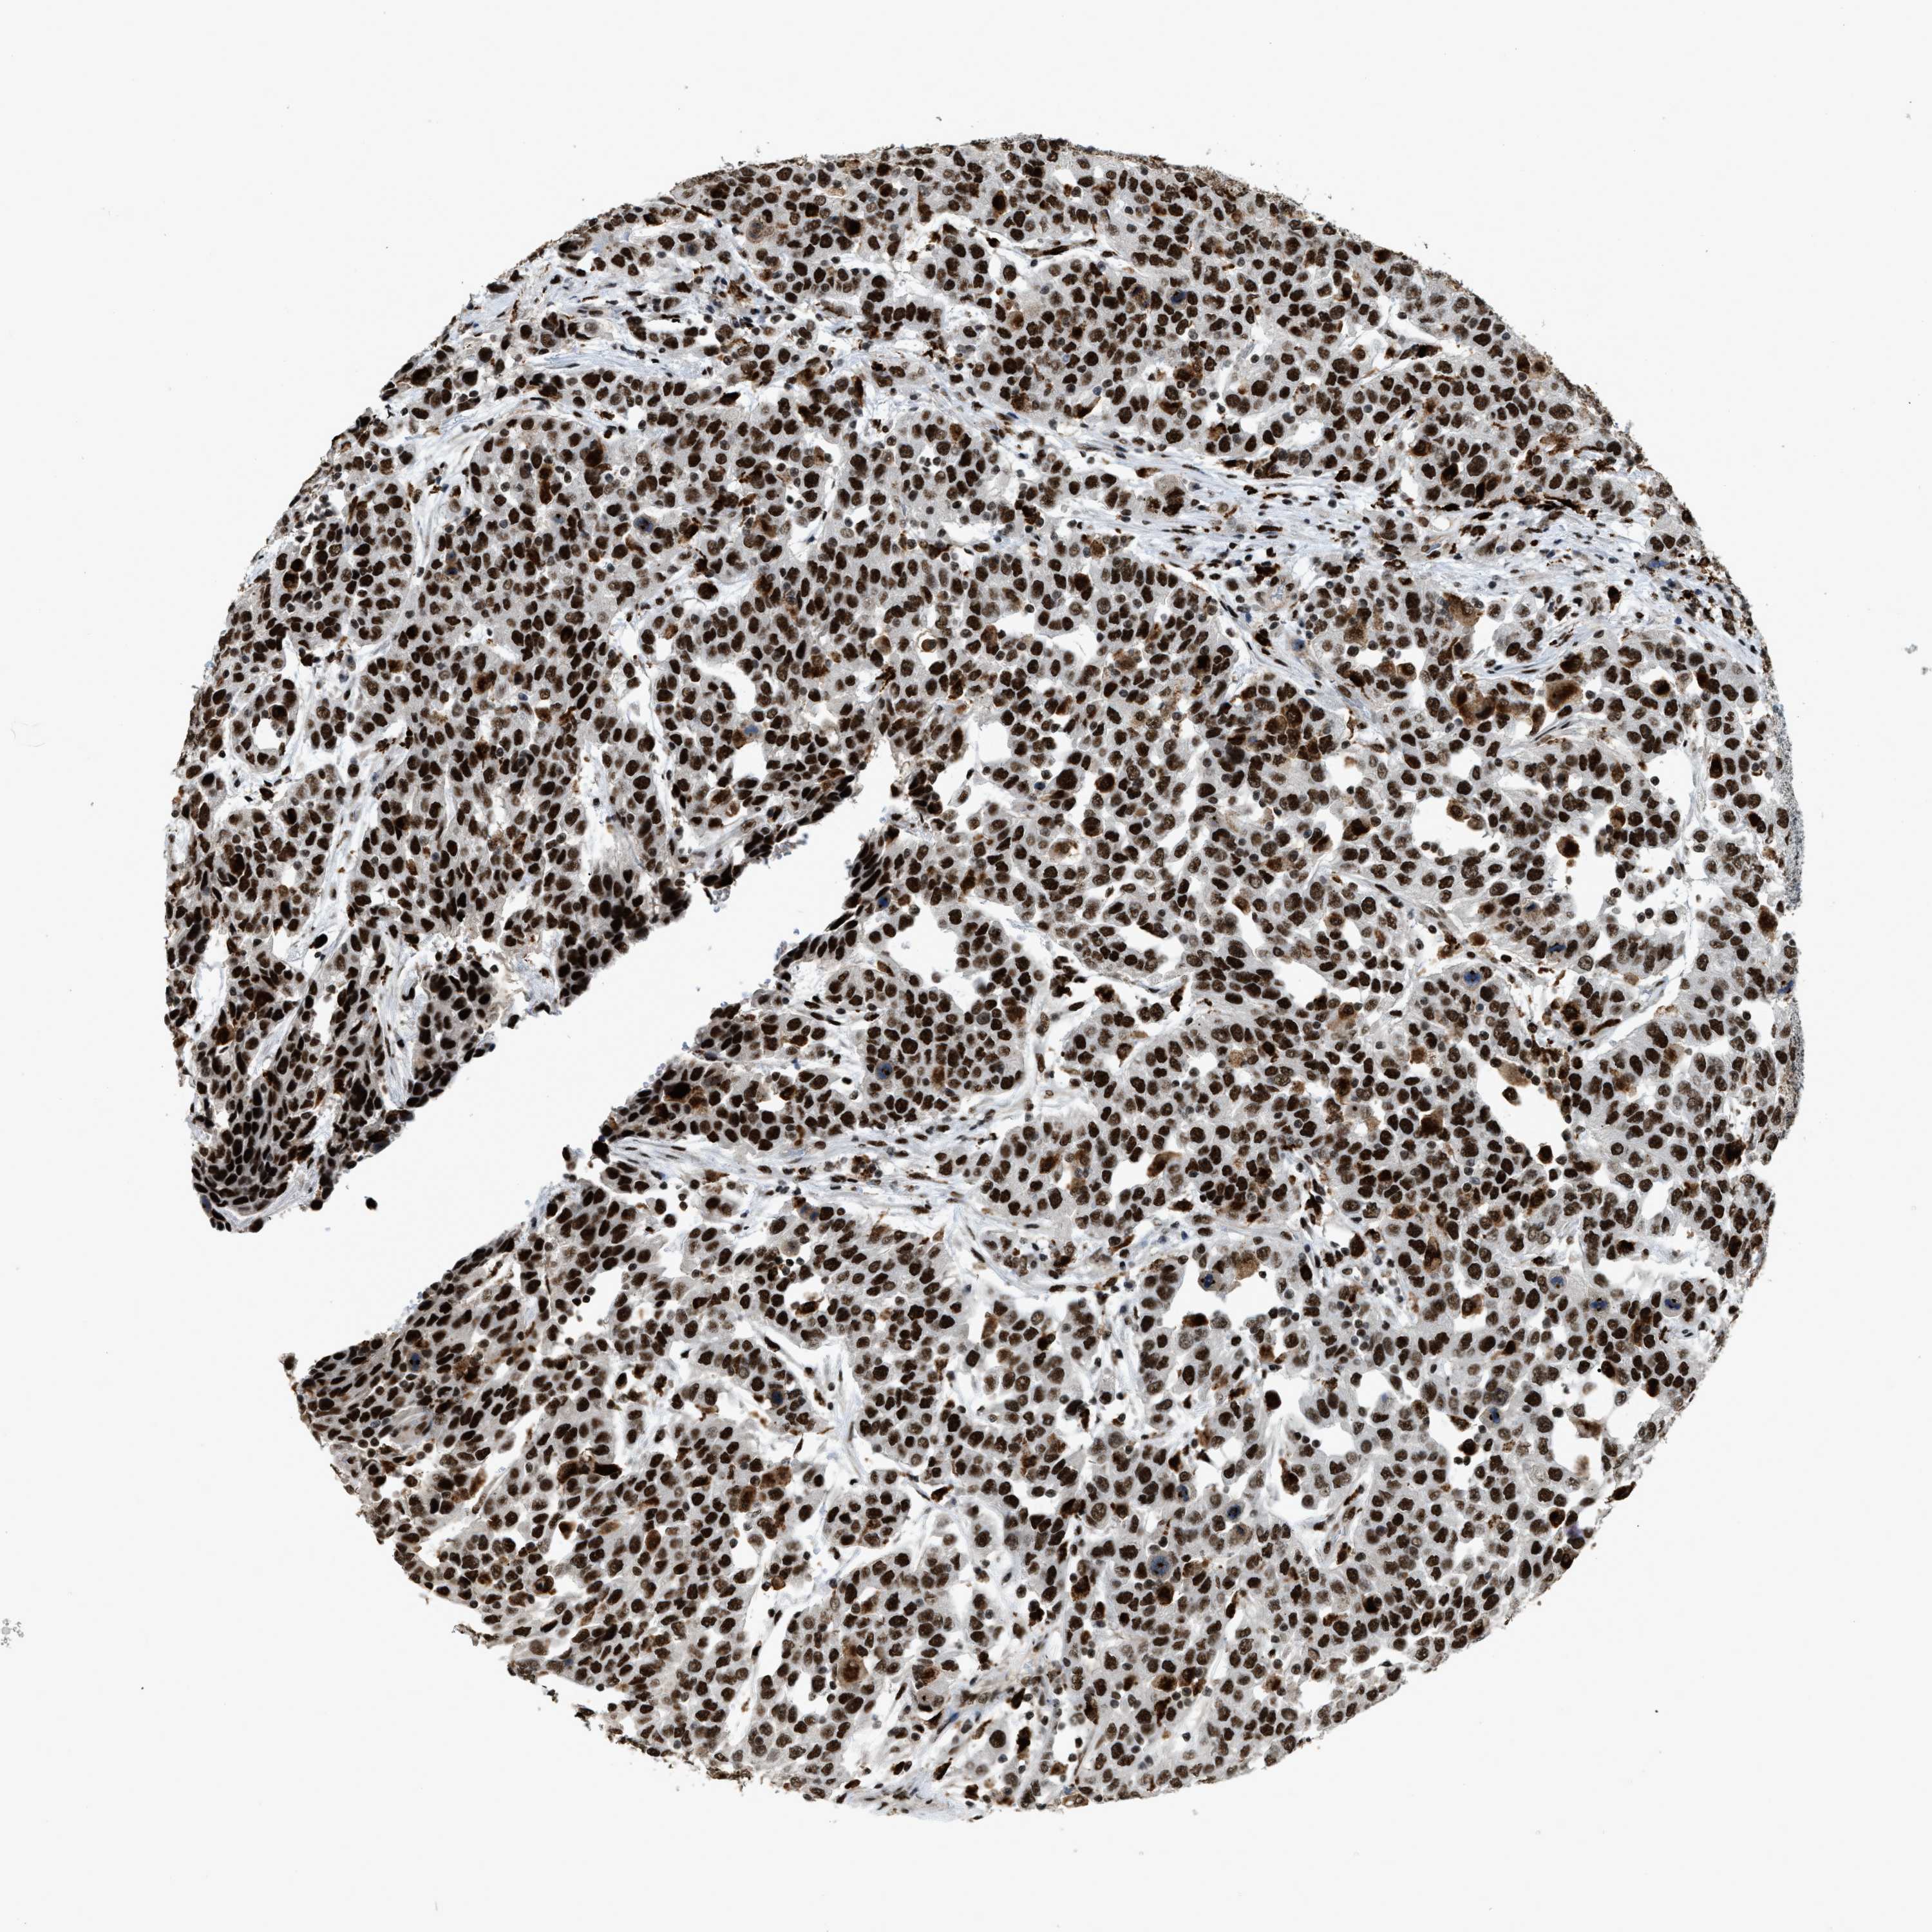

UROTHELIAL CANCER - Protein expressioni

A mouse-over function shows sample information and annotation data. Click on an image to view it in a full screen mode. Samples can be filtered based on level of antibody staining by selecting one or several of the following categories: high, medium, low and not detected. The assay and annotation is described here.

Antibody stainingi

Antibody staining in the annotated cell types in the current human tissue is reported as not detected, low, medium, or high, based on conventional immunohistochemistry profiling in selected tissues. This score is based on the combination of the staining intensity and fraction of stained cells.

Each image is clickable and will lead to virtual microscopy that enables deeper exploration of all samples and also displays staining intensity scores, fraction scores and subcellular localization as well as patient and tissue information for each sample.

Antibody HPA019841

Antibody HPA019859

Antibody HPA029912

Staining

High

Medium

Low

Not detected

Intensity

Strong

Moderate

Weak

Negative

Quantity

>75%

75%-25%

<25%

None

Location

Nuclear

Cytoplasmic/membranous

Cytoplasmic/membranous,nuclear

Urothelial carcinoma, Low grade

Urothelial carcinoma, High grade